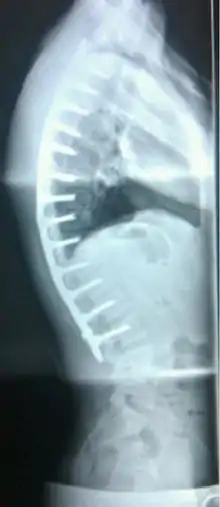

يعد داء شورمان داء عظمي غضروفي، ويعد أيضاً المرض الأكثر شيوعاً المسبب لفرط الحداب الهيكلي التقدمي للفقرات الصدرية أو الصدرية القطنية المصاحب لآلام الظهر خلال فترة سن المراهقة أو البلوغ.[1]

يعتبر الحداب الناشئ من مرض شورمان جامد أو صلب لا يتعدل مع انبساط أو انتصاب الظهر، وهذا عكس الحداب الصدري الوضعي حيث يتعدل مع انبساط الظهر ولا يعد مرضاً.[1]

عام 1964 م تم تعريف المرض على أنه توتد 5 درجات على الأقل من الجهة الأمامية للفقرة الواحدة، لثلاث فقرات صدرية متتابعة بحيث يكون ملاحظ على الصور الشعاعية.[2]

درجة الحداب يتم قياسها باستخدام طريقة زاوية كوب.

- ازدياد الحداب لأكثر من 70 درجة (بحيث لا يمكن الحد من التدهور باستخدام الدعامة) مصاحب لآلام شديدة لا تخف مع المسكنات أو العلاج التحفظي لمدة 6 شهور على الأقل.